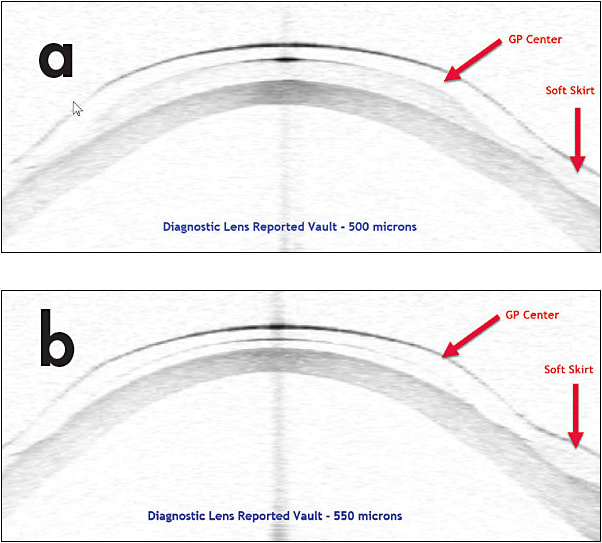

- Excessive vault often leads to a “crash” of the soft skirt. Figure 3 shows that a higher vault of a hybrid contact lens can result in reduced clearance under the lens. If you are unsure whether you have too much clearance, check the fit again after 30 to 60 minutes before finalizing an order. This action can save you a refit during a future office visit. CLS